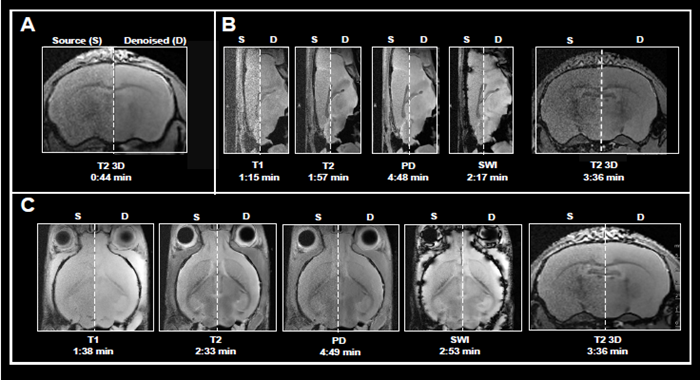

This article shows the application of Smart Noise Reduction to denoise rapid structural brain scans. Fig 4 depicts instances of ex vivo brain scans with various contrasts and orientations collected in less than five minutes. The data was collected from sensors operating at 3, 7, and 9.4 Tesla.

To accomplish the desired short acquisition time, conventional procedures produced for each system were modified to remove averaging (Fig 4A-C). This resulted in 7-15 faster acquisition times than the original protocols.

With the specified resolution, however, no averaging produced noisy images. Reconstructing the obtained data with the denoising algorithm effectively reduced noise from images and produced high-quality results.

Figure 4. Examples of fast brain scans. Ex vivo data of a fixed mouse head acquired with different image contrasts, geometries and orientations. Data were acquired at A) 3 Tesla, B) 7 Tesla, and C) 9.4 Tesla. Images were reconstructed with no denoising (Source) and with a network Strong and applying 50 % pre-denoising and a denoising level of 70 % (Denoised). Image Credit: Bruker BioSpin Group